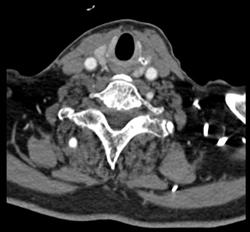

Carotid Artery Stenosis